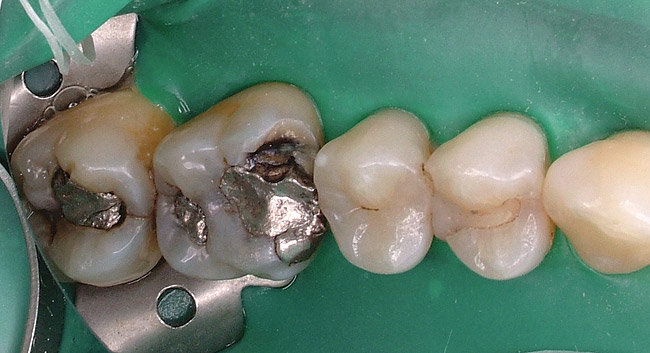

Replacement of existing restorations is responsible for 75% of all operative dentistry.15,19 The reasons for placement and replacement of restorations of direct restorative materials include: primary caries (Figure 1 and Figure 2); recurrent caries (Figure 3); poor margins (Figure 4 and Figure 5); restoration fracture (Figure 6 and Figure 7); tooth fracture (Figure 8); esthetics (Figure 9); non-carious tooth structure lost (attrition, abrasion, abfraction, erosion) (Figure 10); and pain/sensitivity.

Fig. 4 Defective margins. Mandibular first molar with an amalgam restoration with defective margins.

Figure 4  Defective margins. Mandibular first molar with an amalgam restoration with defective margins.

Figure 4